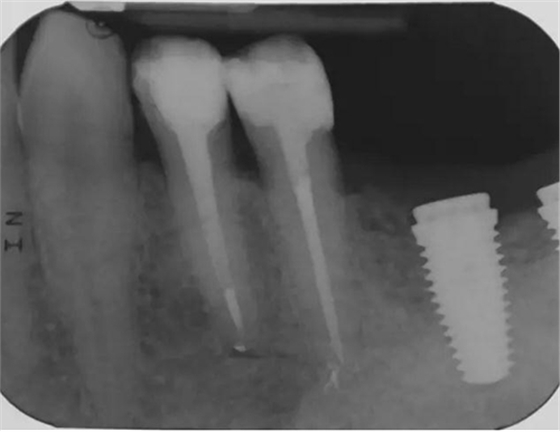

圖4 該病例中,左下4根充失敗,左下5牙髓壞死。兩個牙齒均需要根管治療和修復(fù)。

圖5 根管治療術(shù)后。左下4需要使用纖維樁,并用雙固化樹脂粘結(jié)劑粘結(jié)。左下5無需纖維樁。但2個牙齒均需要進(jìn)行覆蓋牙尖的修復(fù)。

圖7 術(shù)后片。左下4重新疏通。根尖4mm牙膠封閉,根管內(nèi)粘結(jié)了纖維樁。左下5根尖有根分叉。在根管冠段,可以樹脂(SDR)進(jìn)入,輔助固位。